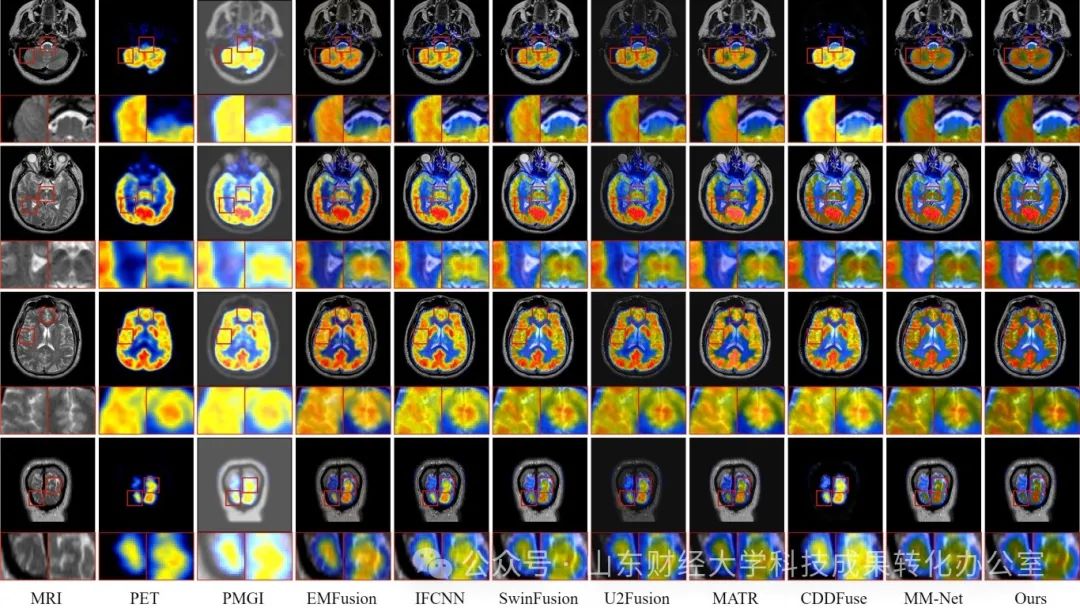

设计了超声图像增强、MRI图像超分辨率等多种智能图像处理方法,提出了多种医学图像融合技术或框架并已申请专利,如结合Swin Transformer和CNN的优势,通过渐进式特征提取和频域信息补充,实现MRI和CT等多模态医学图像的融合,提高了图像融合的准确性和效率,能够获取更丰富的医学图像信息,为医生提供更全面的诊断依据。